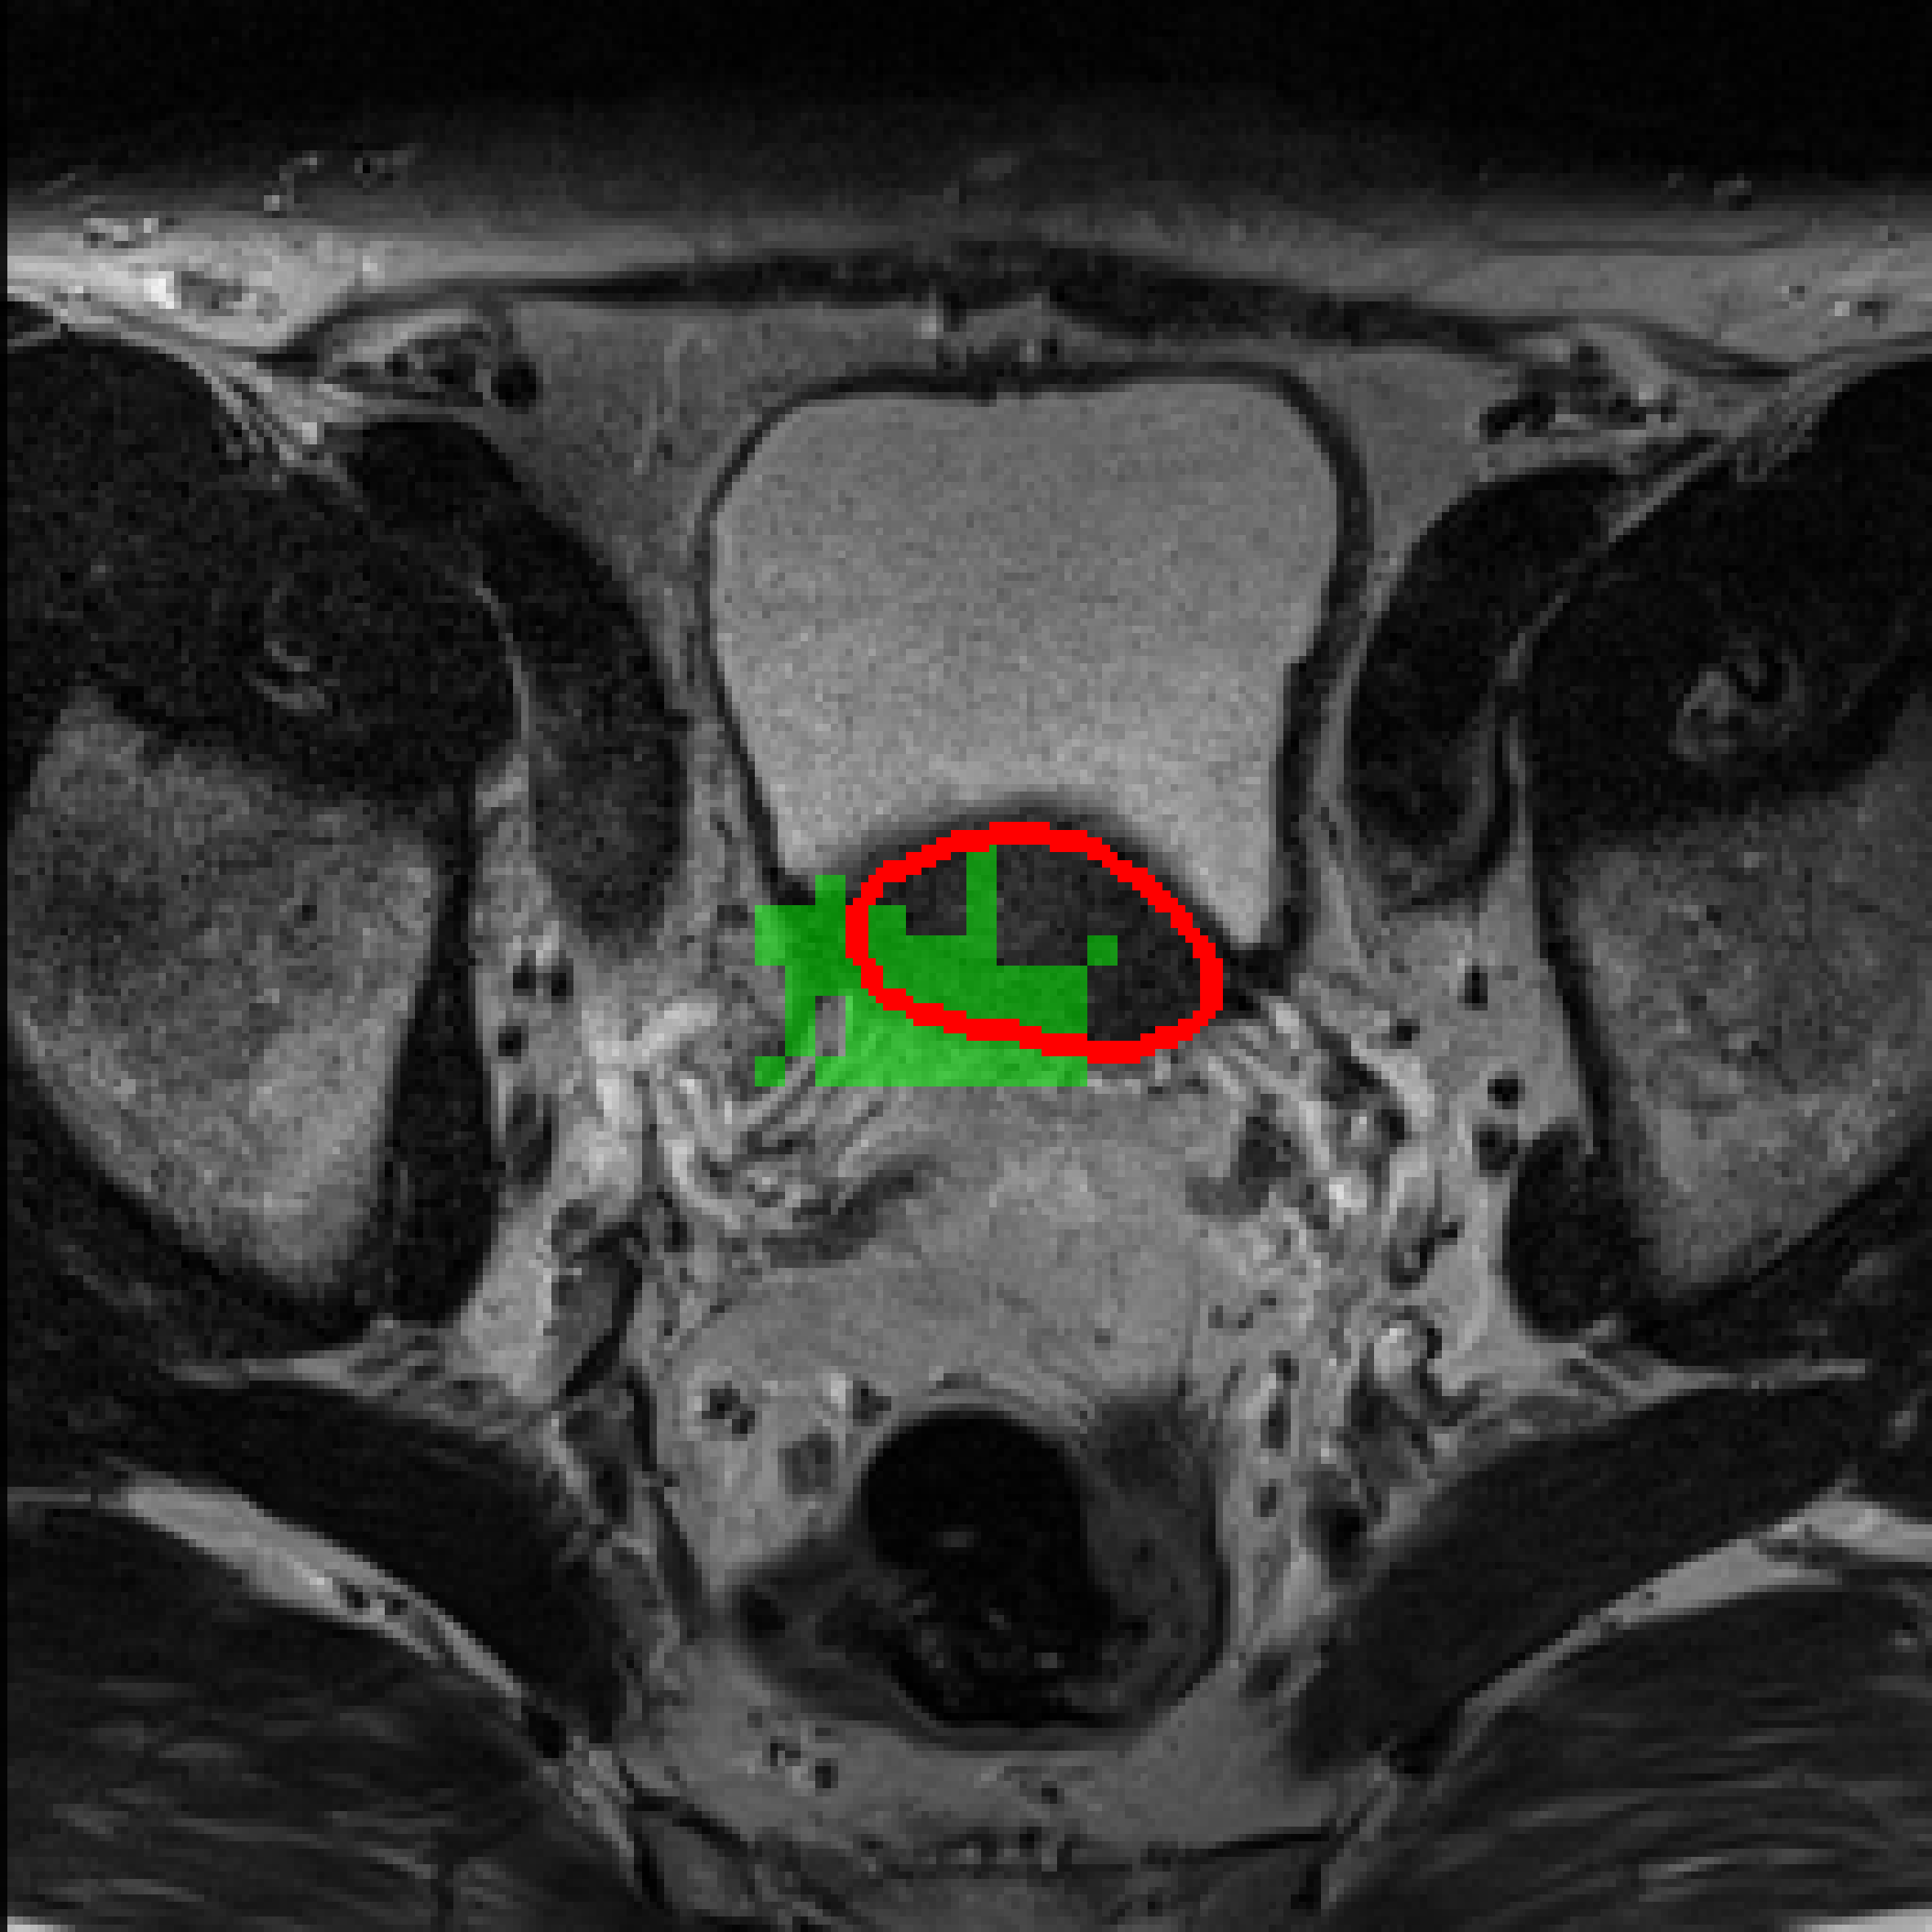

Table 3: Qualitative results of different methods, \Circle and \CIRCLE denote groundtruth and predicted mask, respectively.

SAM MedSAM SAM-Med2D CPC-SAM KnowSAM Ours

5% Promise [Uncaptioned image] [Uncaptioned image] [Uncaptioned image] [Uncaptioned image] [Uncaptioned image] [Uncaptioned image]

10% Promise [Uncaptioned image] [Uncaptioned image] [Uncaptioned image] [Uncaptioned image] [Uncaptioned image] [Uncaptioned image]

5% Colon [Uncaptioned image] [Uncaptioned image] [Uncaptioned image] [Uncaptioned image] [Uncaptioned image] [Uncaptioned image]

10% Colon [Uncaptioned image] [Uncaptioned image] [Uncaptioned image] [Uncaptioned image] [Uncaptioned image] [Uncaptioned image]

For the qualitative results shown in Tab. 3, our method consistently produces more accurate and compact segmentation results for most cases in the PROMISE12 and COLON datasets, effectively capturing the prostate and polyp boundaries while suppressing background noise. In contrast, other approaches tend to over-segment the target regions, leading to the inclusion of irrelevant surrounding tissues. These results visually demonstrate the robustness of our method in handling diverse anatomical variations.